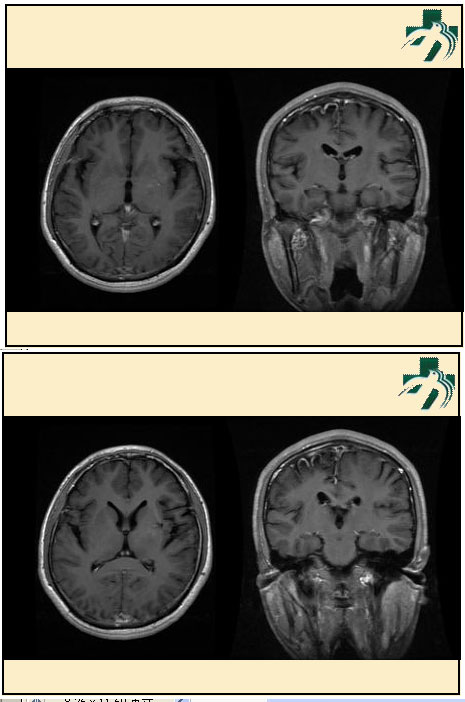

奴卡氏菌感染

第九期三博

读片会

病例之四

北京协和医院 提供

男性,22岁。自觉虫咬后皮疹、肢体麻木4月